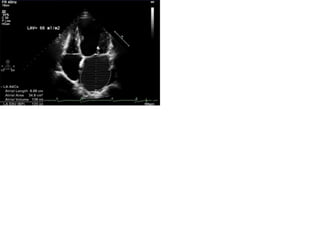

Morfología al ECO TT

• Engrosamiento y calcificación de los velos

• Doming del velo anterior y disminución del movimiento del

posterior

• Fusión de las comisuras y de las cuerdas tendinosas

• Aumento de tamaño de la AI

• Trombos

• HAP

• Eje largo y eje corto e busca de signos reumáticos

– Fusión de comisuras (apertura en cúpula)

– Acortamiento y fusión de las cuerdas tendíneas

• Movilidad velos de la válvula mitral

• Engrosamiento del aparato valvular

• Calcificación

• Enfermedad subvalvular